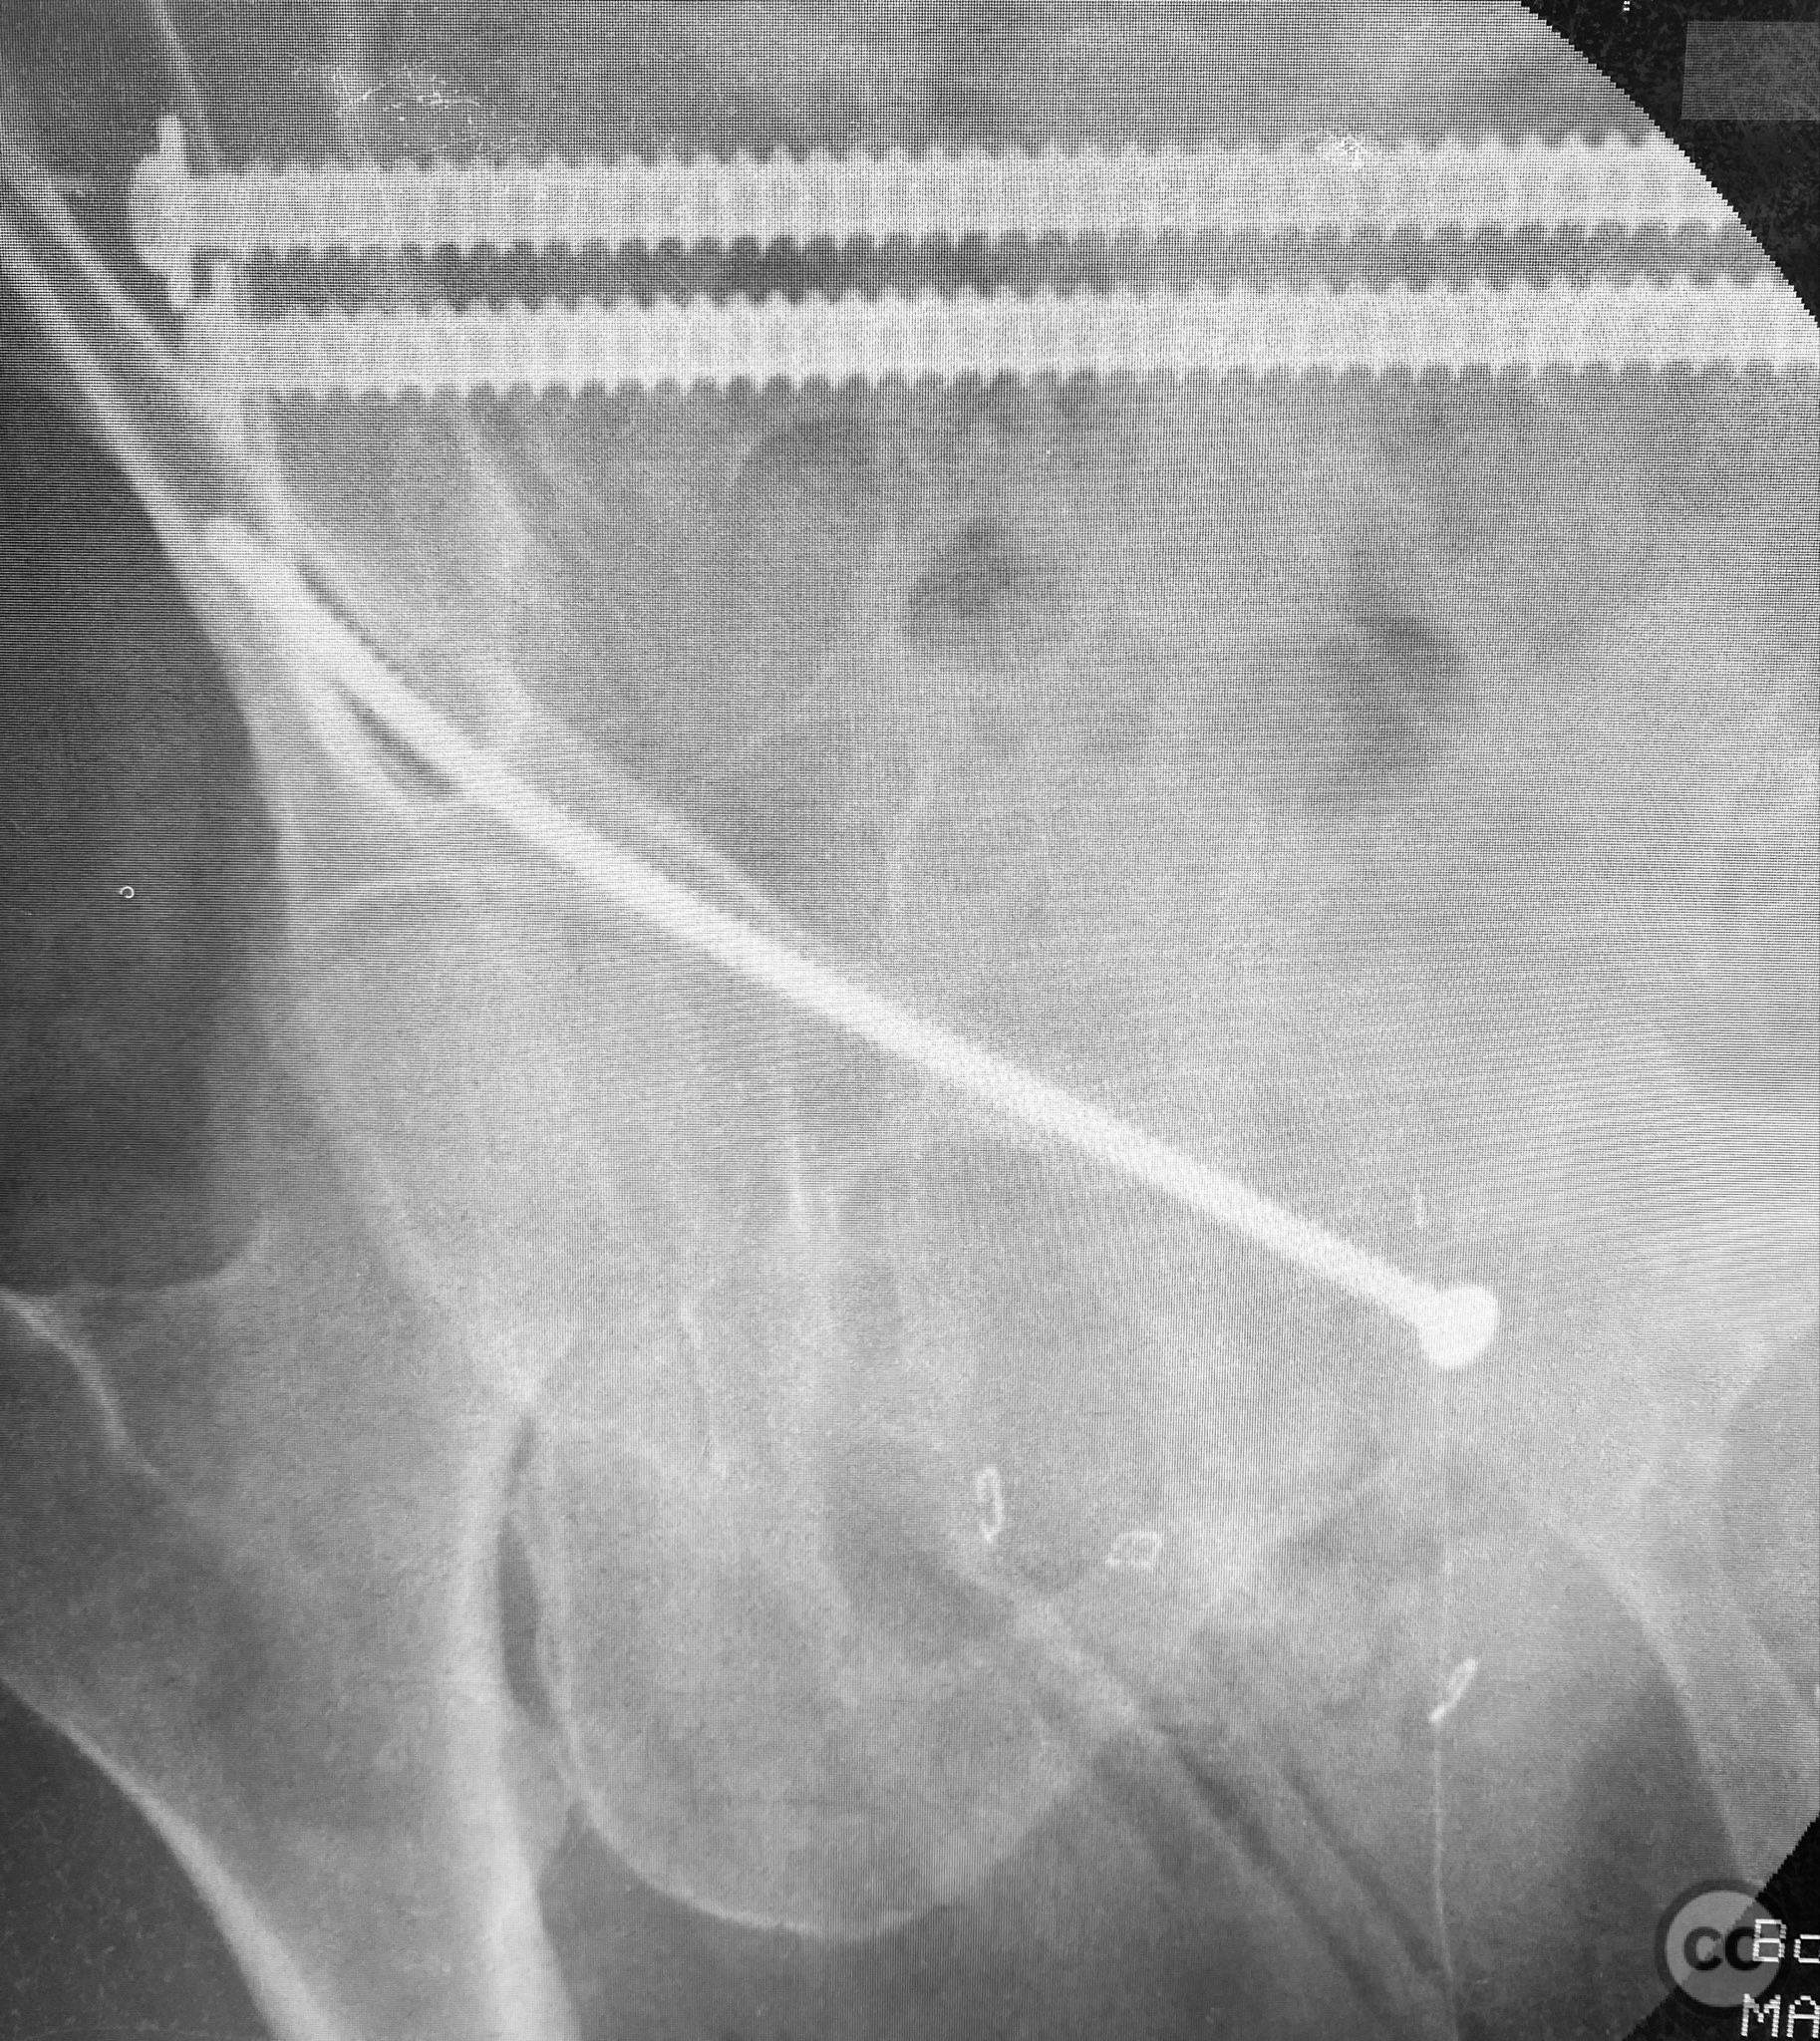

Anatomical surgical approach:  For the posterior fixation, a percutaneous approach was utilized targeting the upper sacral ala, with stab incisions made over the posterior superior iliac spine and blunt dissection to bone. Under fluoroscopic guidance, guidewires were advanced across the sacroiliac joint into the S1 body, followed by cannulated IS screw insertion. For anterior fixation, a small incision was made over the pubic tubercle, and a 4.5mm blunt tip cortical screw was introduced retrograde along the superior pubic ramus isthmus under fluoroscopic control, advanced by screwdriver along the dense lateral iliac bone.

Intraoperatively, EUAF confirmed instability sites and allowed dynamic assessment of reduction. IS screws were placed in the upper sacral path for posterior stabilization. The anterior ring was stabilized with a retrograde 4.5mm blunt tip cortical screw, advanced by turning with a screwdriver, utilizing the variable width of the ramus isthmus for optimal implant fit and stability. The technique permitted percutaneous fixation with minimal soft tissue disruption.

Orthopaedic implants used:   7.0mm cannulated iliosacral screws; 4.5mm blunt tip cortical threaded screw